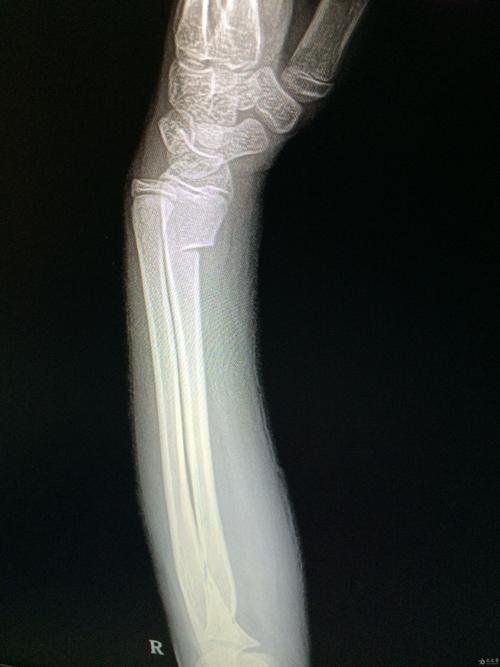

小儿桡骨远端青枝骨折

手腕青枝骨折